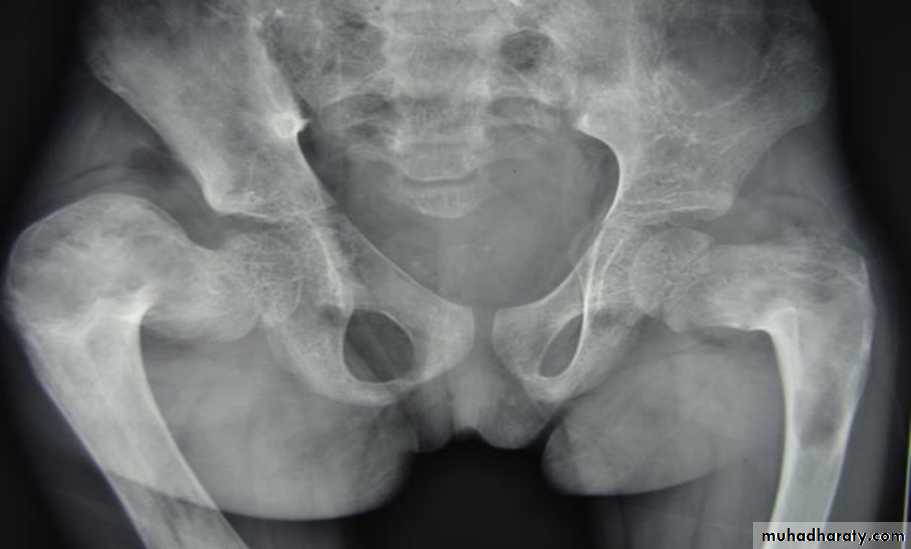

Brown tumor more common in the primary type seen as lytic expansile lesion in any bone particularly the mandible & pelvis.

*Triradiate pelvis in which pelvic side walls bend inward (sever cases of osteomalasia )

* Looser's zones these are thin short lucent lines with sclerotic margins running across the cortex at right angle, best seen in the scapula , femoral neck , pubic rami (osteomalacia )